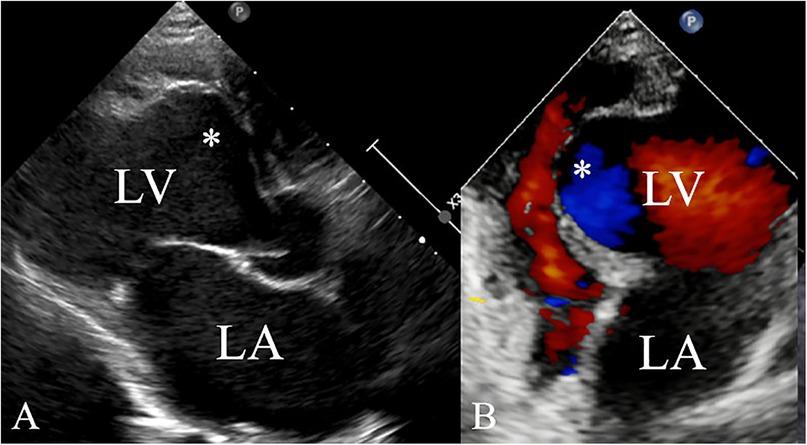

A 5-year-old boy presented with a history of cough and two fever episodes within 3 weeks. Upon admission, his vital signs were stable (T: 36.5 ℃, HR 98 bpm, RR 20 bpm). A physical examination showed the absence of wheezing, with notable cardiothoracic findings. These findings included precordial prominence, cardiomegaly on percussion (documented as 0.5-cm lateral displacement of the apical impulse from the left midclavicular line at the 5th intercostal space), and a regular cardiac rhythm without audible murmurs. His personal history (including prenatal examinations) and familial medical histories were noncontributory. A chest x-ray showed an enlarged cardiac shadow and pneumonia. Electrocardiographic findings included abnormal Q-waves, with visible Q-waves in leads II, III, aVF, and V2–V4. Additionally, ST segment changes were observed (ST segment elevation of 0.1–0.2 mV in leads V1–V4) (Figure 1A), along with QTc prolongation, left atrial heterogeneity, and double-compartment hypertrophy. Echocardiography indicated left cardiac enlargement [Left atrial volume = 28.3 ml (Z score = 4.0), LVend-diastolic diameter = 42 mm (Z score = 5.6)], a ventricular septal aneurysm in the basal and intermediate segments measuring 30 mm × 13.8 mm × 19.0 mm (Figure 2), and biventricular myocardial non-compaction with decreased LV dysfunction [ejection fraction (EF) = 40%, average E/e' = 15.4]. Computed tomographic angiography was systematically conducted for an accurate morphological assessment of the ventricular aneurysm (including topographic localization, volumetric measurement, and perianeurysmal anatomy). This technique showed left cardiac enlargement, increased trabeculation in both ventricles with a grid-like pattern, and fat density shadows within the ventricular septal myocardium (Figure 3), and a ventricular septal aneurysm. A Holter electrocardiogram showed an accelerated atrial escape rhythm (Figure 1B). Magnetic resonance imaging showed left cardiac enlargement [Left atrial volume = 34.82 ml (Z score = 4.9), LV end-diastolic volume = 76.41 ml (Z score = 4.1)], local aneurysm formation in the ventricular septum, biventricular myocardial non-compaction, and fatty infiltration in the middle and apical regions of the LV septum (Figure 4). LV systolic function was impaired (LV ejection fraction = 41.1%) and the right ventricular ejection fraction was normal (55.4%). First-pass perfusion imaging showed a perfusion defect in the ventricular septum of the mid-left ventricle and apex. Delayed enhancement imaging indicated myocardial fibrosis in the above area, which was likely secondary to myocardial ischemia.

Figure 2. Ventricular aneurysm (*) detected by echocardiography (A) of the left ventricle in the long-axis view and (B) the apical four-chamber view.